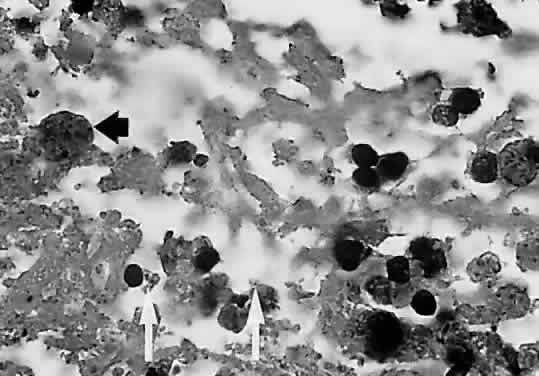

The lesions of ocular toxoplasmosis (Fig. 1) can be important causes of blindness, particularly if they involve the macula, the papillomacular bundle, or the optic nerve. Occasionally, a large peripheral lesion casts off so much inflammatory material into the overlying vitreous humor that vision is affected. In some cases, inflammation initiates organization of the vitreous body; on subsequent contraction of the fibrous bands within this inflammatory mass, tearing of the retina may occur and retinal detachment may ensue.

Fig. 1. The characteristic lesions of toxoplasmic retinochoroiditis in the fundus of an adult. Black arrow denotes active lesion with indistinct borders. White arrow denotes healed “satellite lesions.” (O'Connor GR: Ocular toxoplasmosis. In Locatcher-Khorazo D, Seegal BC (eds): Microbiology of the Eye. St Louis, CV Mosby, 1972.)